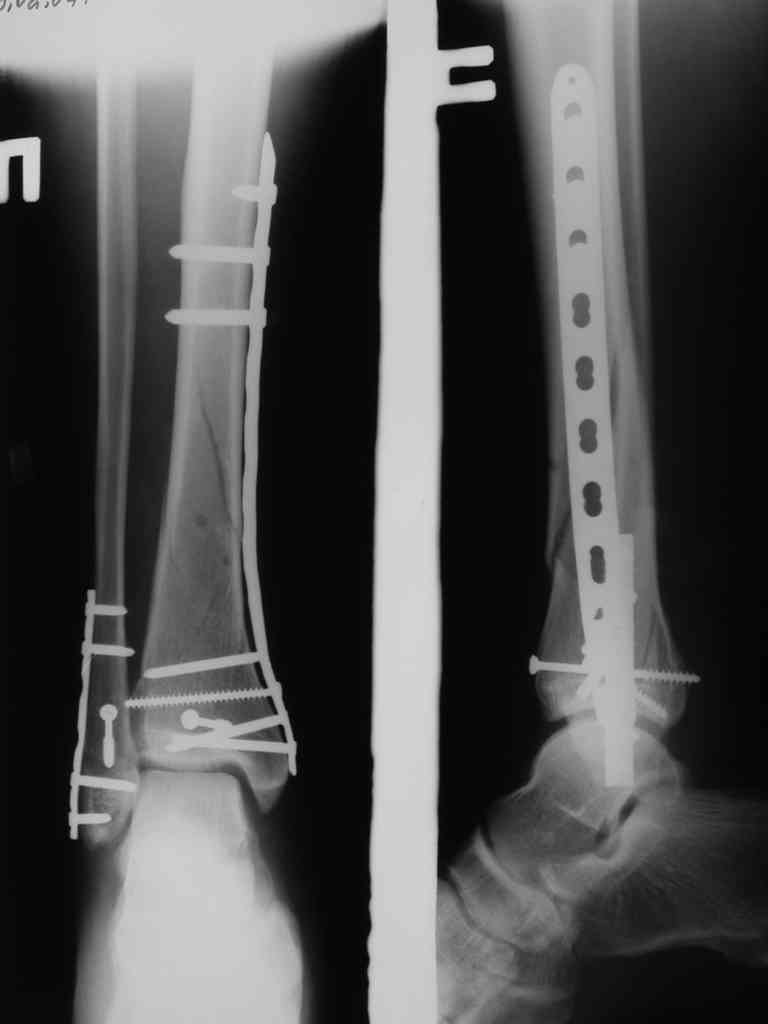

Re: Сложный внутрисуставной перелом голени

Очень много разрезов, большая длительность операции, в итоге нестабильная фиксация, требующая доп. внешней иммобилизации. Высокий риск инфекции.

Мы бы фиксировали пластиной м/берцовую кость открыто, на б/берцовую пластину MIPO, при необходимости сустав открыть минимально.

На фото простой суставной, метафиз. оскольчатый с переходом на диафиз перелом, пластина MIPO.